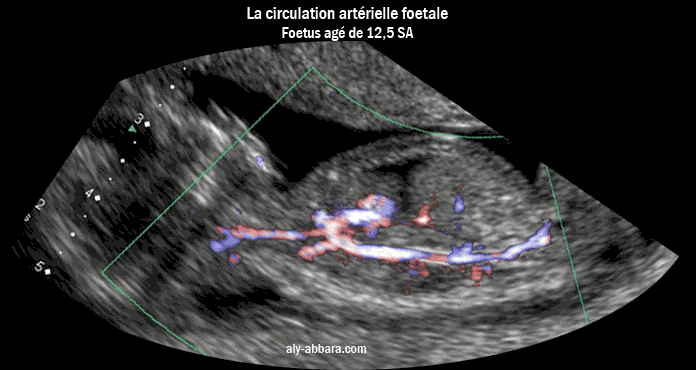

Image échographique analysant la circulation sanguine artérielle chez

un ftus de 12,5 semaines d'aménorrhée (10 semaines et 3 jours de gestation)

Cette analyse est possible grâce à la nouvelle technologie Doppler (Dynamic Flow)